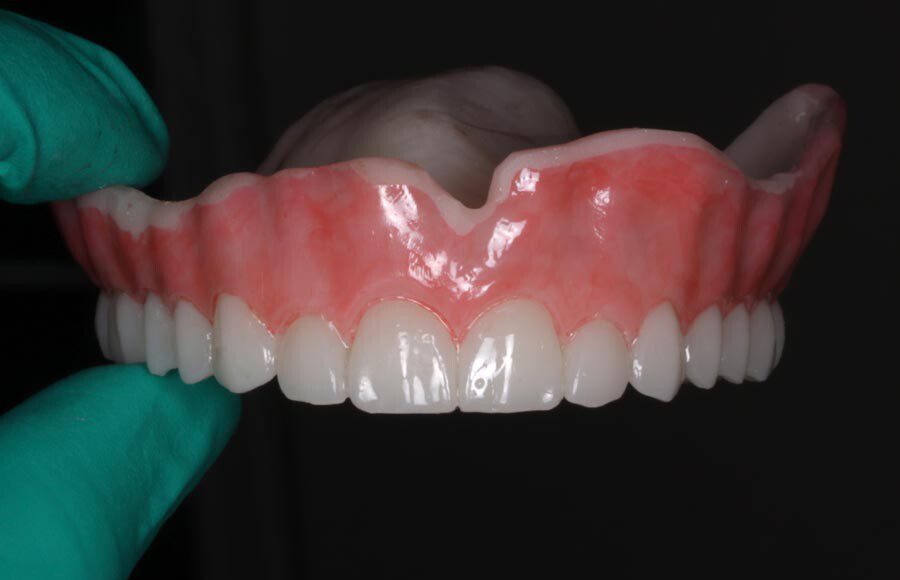

Smile GalleryImplant RestorationsImplant Dentures Post-op smiling 1 of 32 Pre-op close up smiling Pre-op lips retracted smiling Pre-op panoramic x-ray Implants in upper jaw (occlusal view) Implants in lower jaw (occlusal view) Panoramic x-ray of implants First set of try-ins – upper denture First set of try-ins – lower fixed provisional Delivered try-ins (lips retracted) Close adaptation to gums and appropriate emergence profile of lower fixed provisional Gum tissues have been molded by a convex provisional Delivered try-ins Second set of try-ins (lips retracted) Close adaptation to gums and appropriate emergence profile of second set of lower fixed provisional Delivered second try-ins Definitive restorations on casts (frontal view) Definitive restorations on cast (right side) Definitive restorations on cast (left side) Definitive upper overdenture (occlusal view) Definitive lower fixed titanium-acrylic hybrid restoration (occlusal view) Definitive lower fixed titanium-acrylic hybrid restoration (frontal view) Definitive lower fixed titanium-acrylic hybrid restoration (tissue side view) Healthy molded gum tissues on lower prior to delivery of lower fixed hybrid restoration Healthy gum tissues on upper prior to delivery of upper overdenture Definitive restorations (frontal, lips retracted) Definitive lower restoration (frontal) Definitive restorations (right side) Definitive restorations (left side) Definitive lower restoration (occlusal view) Definitive upper restoration (occlusal view) Post-op panoramic x-ray Post-op smiling